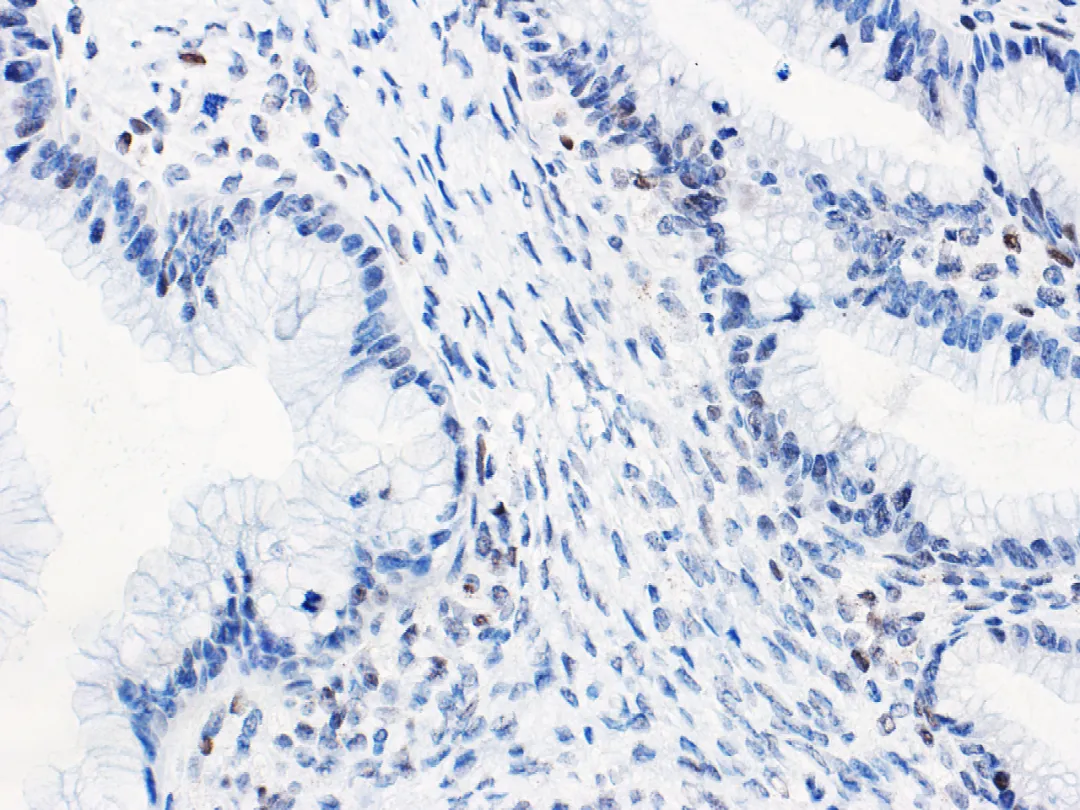

The accuracy of immunohistochemical p53 results in predictingTp53gene mutation in ovarian mucinous tumors (as shown in Figure 3) is also relatively high. It indicates thatTp53gene mutation is associated with the progression of ovarian mucinous borderline tumors. Evaluating p53 status in a large number of ovarian mucinous tumors by immunohistochemistry did not find an association with prognosis. However, immunohistochemical p53 results in a small number of mucinous borderline tumors are associated with an increased risk of death. Although treatment options for such patients are limited, normal p53 immunohistochemical expression suggests a lower risk of progression in mucinous borderline tumors with unusual clinical manifestations (e.g., tumor rupture).

Figure 3. Ovarian seromucinous carcinoma – Wild-type p53 normal expression